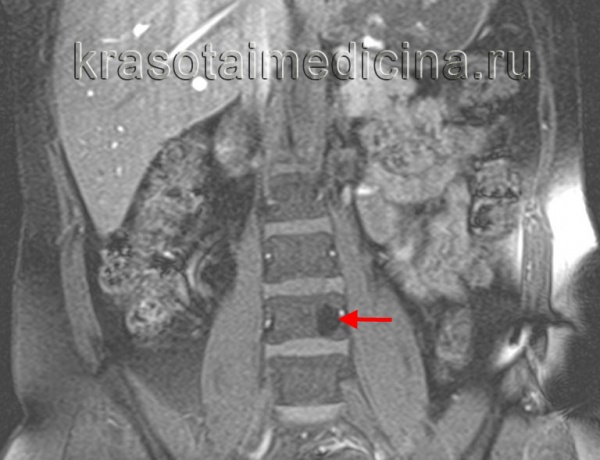

(Справа) Сагиттальный срез, Т1-ВИ: бедная жировой тканью гемангиома L5 позвонка, характеризующаяся диффузной гипоинтенсивностью сигнала тела позвонка Также визуализируется вентральный эпидуральный компонент, сдавливающий дуральный мешок, характеризующийся смешанной интенсивностью сигнала жировой ткани и мягких тканей, представляющий собой экстраоссальный компонент гемангиомы.